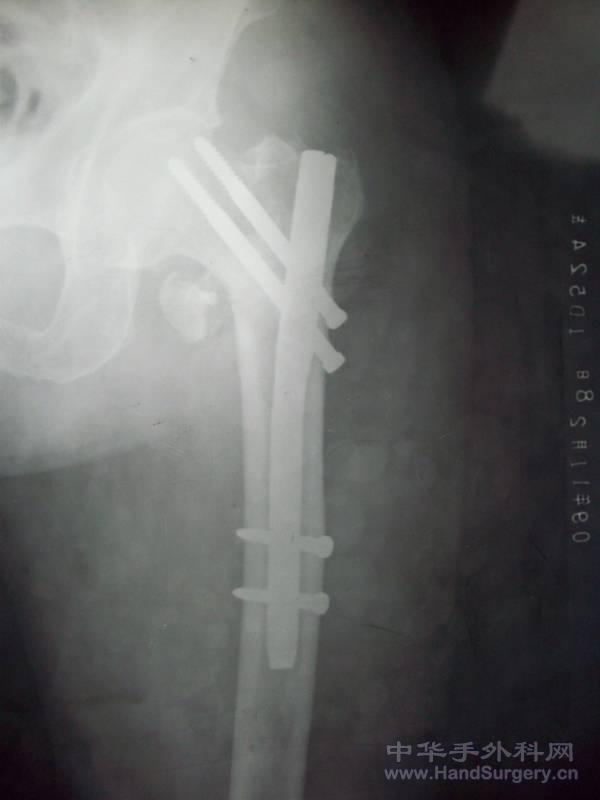

看张片子,PFN. 100_1491.JPG

不完美啊,PFN上面的两针角度有点太斜哎,全髋还可以,看片子股骨颈全截了?